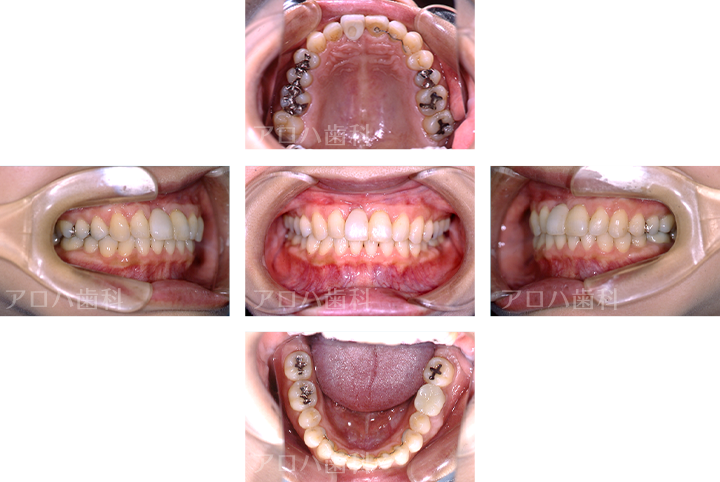

CASE02/30代女性

初診時

治療終了後3年時

| 主訴 | 右の前歯が折れた、矯正治療もしたい |

| 治療内容 | 転んで前歯を失った方です。 下の前歯もガタガタが気になるとのことで、矯正治療と並行してインプラント治療を行いました。 治療後3年間経過していますが、ほとんど骨吸収なく順調な経過をたどっています。 |

| 治療期間 | 6か月 ※矯正治療期間は別途 |

| 治療費用 | 605,000円 ※矯正治療費用は別途 |

| 費用詳細 | ・サージカルガイド 55,000円 ・GBR 110,000円 ・インプラント手術+アバットメント+上部構造 440,000円 |